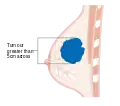

Stage T1 breast cancer

Stage T2 breast cancer

Stage T3 breast cancer

Metastatic or stage 4 breast cancer